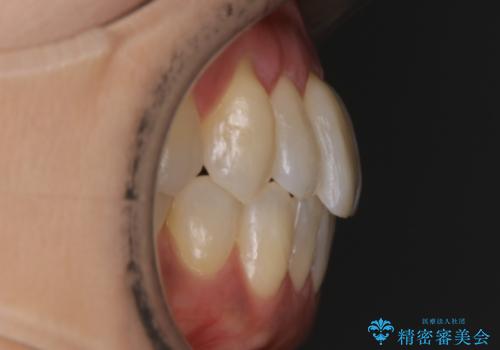

【非抜歯】短期間で実現する前歯の反対咬合治療

- 前歯のガタつきを主訴に来院されました。

奥歯の噛み合わせにはほとんど問題が見られず、歯列拡大とIPRのみの必要最低限の移動で歯並びの治療を計画することとなりました。

拡大とIPR

歯列の幅を拡大することにより作れるスペースは想像より大きく、実際に拡大だけでガタつきが治せるというケースもあります。

その他の歯のガタつきをとるためのスペース作りの方法の一つにディスキング(IPR)という方法があります。

歯と歯の間を一ケ所あたり最大0.5mmまでの範囲内で削ることで歯自体が少し小さくなり、それにより作られるスペースを数ヶ所分合わせることで合計で数mmの大きなスペースが作れるという方法です。